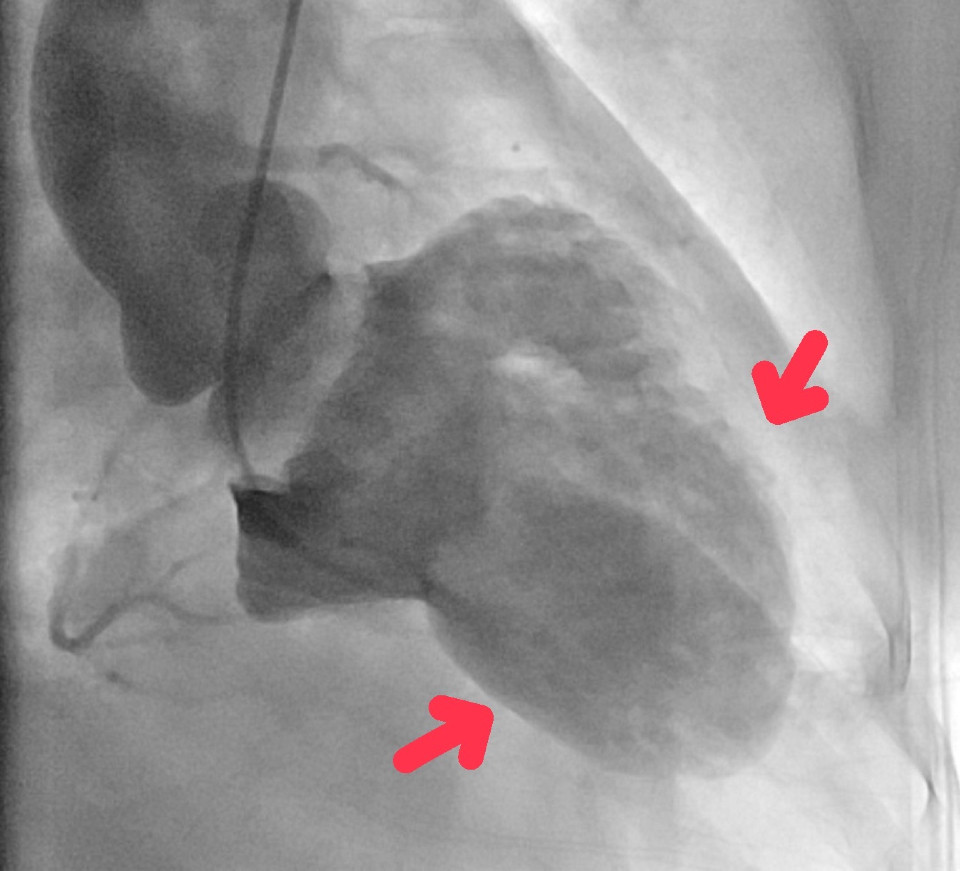

郭醫師說明,在心導管檢查中,心臟冠狀動脈攝影並沒有看到阻塞的血管,也就是說,不是心肌梗塞,但是在左心室攝影圖(Left Ventriculography)下,左心室收縮時的形狀看起來像是日本漁夫在捕捉章魚時用的章魚壺陷阱,當下的診斷為章魚壺心肌症(Takotsubo Cardiomyopathy) ,俗稱為「心碎症候群」,患者在住院過程恢復良好,於10天後康復出院。

「心碎症候群」乍聽之下有種淒美之感,在醫學上稱之為章魚壺心肌症,患者的心臟左心室收縮時沒有往內縮,而是呈現章魚壺的形狀,這類患者往往是經歷了極端的情緒和壓力變化,可能是生理或是心理壓力,體內突然產生大量的兒茶酚胺,造成心臟無法負荷快速增加的壓力而導致心臟出現病變,左心室沒有正常收縮,堵住了血流的出路。